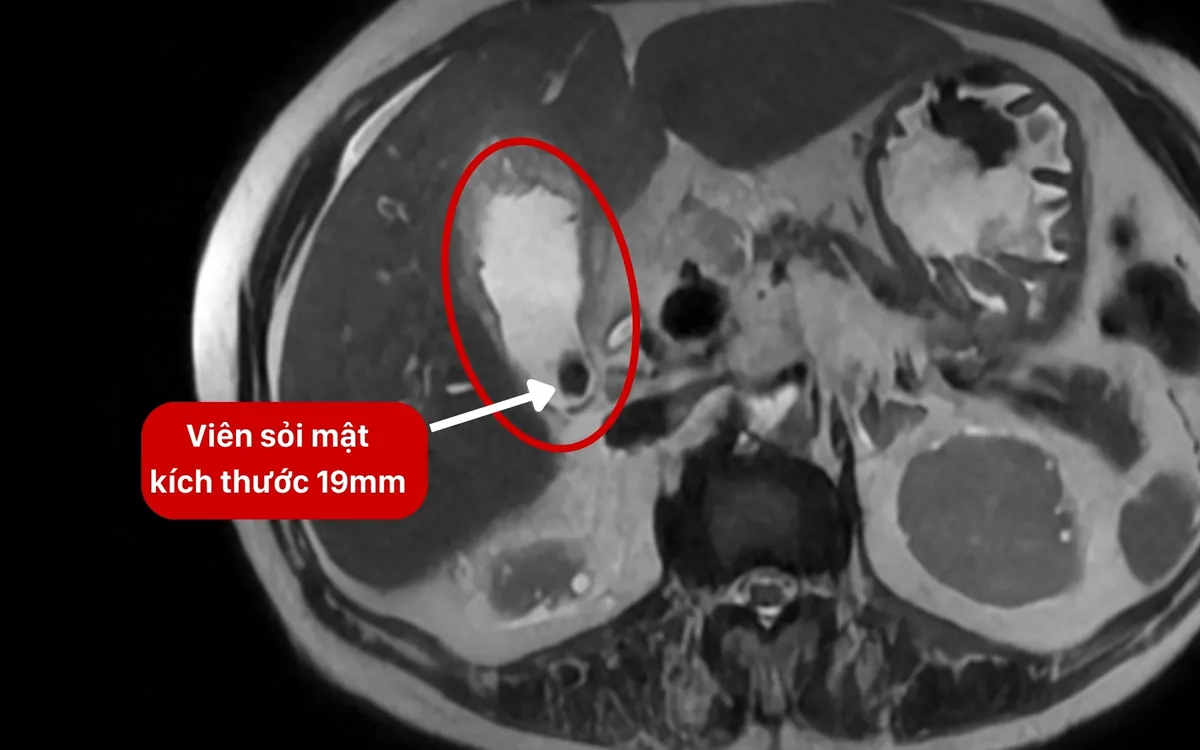

Kết quả kiểm tra cho thấy các chỉ số viêm và nhiễm khuẩn đặc hiệu tăng vọt ở mức báo động, trong đó CRP tăng gấp 73 lần và PCT tăng tới 927 lần so với bình thường. Hình ảnh chẩn đoán ghi nhận túi mật giãn lớn, thành dày khoảng 1cm; ở cổ túi mật có viên sỏi kích thước 19mm kẹt chặt, kèm theo tình trạng thâm nhiễm và tụ dịch lan rộng quanh túi mật, lan tới khoang gan – thận.

Hình ảnh viên sỏi kích thước 19mm kẹt ở cổ túi mật